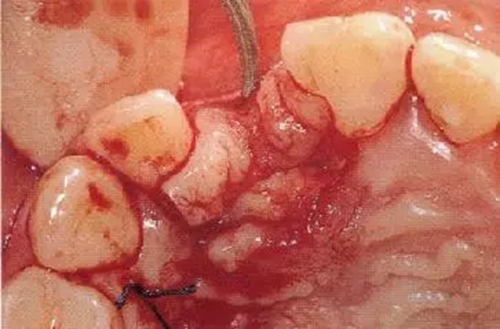

▲圖44-7,8

7個(gè)月后,牙齦組織的愈合狀態(tài)。

▲圖44-9

種植體的理想植入位置

該位置可以通過粘接劑接合的方式進(jìn)行前牙區(qū)修復(fù)處理

▲圖44-10

▲圖44-11

圖44-9~11 種植體植入時(shí)的狀態(tài)。將種植體邊緣植入低于兩鄰牙的牙齦線連線3mm的位置。頰舌方向則位于距唇側(cè)CEJ1mm的位置。